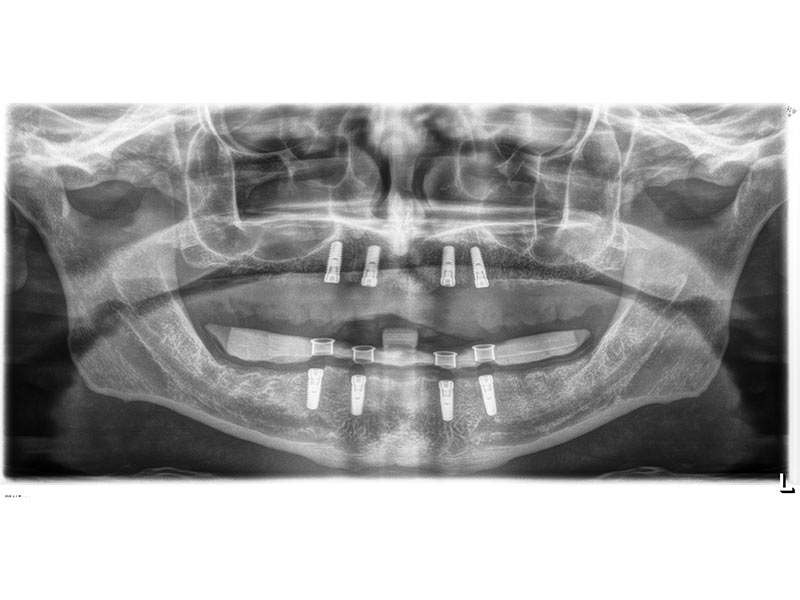

Zahnimplantate werden anhand von moderner virtueller 3D-Planung passgenau geplant und inseriert. Der Vorteil von Implantaten besteht darin, dass festsitzender ästhetischer Zahnersatz auch in solchen Fällen realisiert werden kann, in denen sonst nur herausnehmbare Prothesen möglich wären. Zudem ist im Gegensatz zur Brückenprothetik kein Beschleifen der Nachbarzähne notwendig.

Unter dentalen Implantaten versteht man im allgemeinen eine Schraube, die dort, wo ein oder mehrere Zähne verloren gegangen sind, in den Kieferknochen "eingepflanzt" wird. Diese Therapieform der Implantologie hat sich in den letzten Jahren zu einem alltäglichen Therapieverfahren in der Zahnheilkunde entwickelt. Wissenschaftliche Untersuchungen zeigen hierfür eine Erfolgsquote von i. d. R. 80-98 % über 10 Jahre. Verglichen mit anderen zahnärztlichen Maßnahmen gibt es nahezu keine andere Therapie mit derart guten Erfolgsaussichten. Auch eine Verbesserung der Lebensqualität wird durch implantatgetragenen Zahnersatz laut klinischer Studien erreicht.